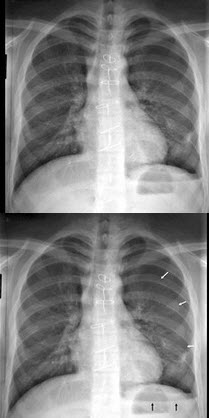

B.广告市场

83、单项选择题

根据图像,最可能的诊断是()

A.肺气肿

B.慢性支气管炎

C.气胸

D.纵隔气肿

E.肺转移瘤